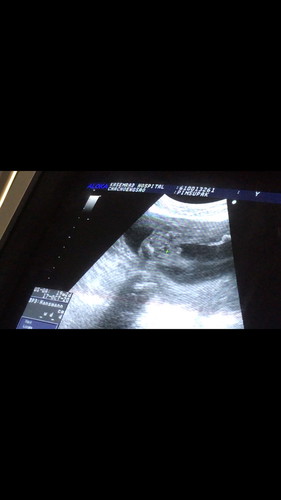

ช่วยดูหน่อยจ้า ผู้ชาย100%มั้ยคะ

คุณหมอบอกว่าจะไม่ชัวร์ว่าผู้ชาย100%คะ. แอบลุ้น?

ผช.นะคะแม่ ไข่น้องค่อยข้างชัด

คิดว่าผู้ชายค่ะแม่